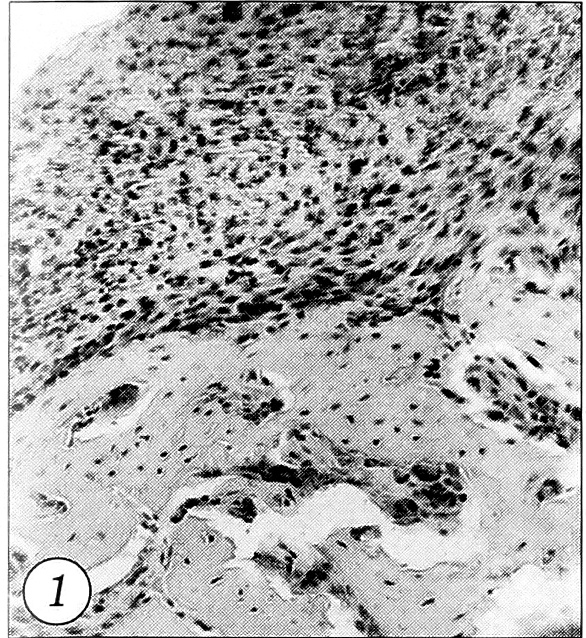

Во 2-й (контрольной) группе животных на 3-и сутки после перелома у поверхности отломков кости определялась выраженная полиморфно-клеточная инфильтрация с доминированием нейтрофильных лейкоцитов и лимфоцитов (рис. 1). Отмечалось появление крупных остеобластов. В мягких тканях, окружающих отломки кости, имелись признаки кровоизлияния. При ТЭМ среди клеток крови, где доминировали эритроциты, на 3-и сутки определялось большое количество микроорганизмов, которые располагались между эритроцитами, не пе-нетрировали их и сами не претерпевали видимых изменений (рис. 2). Максимальное количество микроорганизмов в зоне перелома и окружающих отломки кости мягких тканях определялось на 3-и сутки после перелома. В местах наибольшего скопления микроорганизмов, среди которых различались как палочки, так и кокки, выявлялись многочисленные фрагменты деструктивно-измененных клеток. В этих участках фагоциты (как макро-, так и микрофаги) не обнаруживались (рис. 3).

Рис. 1. Выраженная полиморфно-клеточная инфильтрация на поверхности кости и в межтрабекулярных пространствах, нарушение архитектоники кости. 3-и сутки после перелома, контрольная группа (окраска гематоксилином и эозином, об. 10, ок. 10).